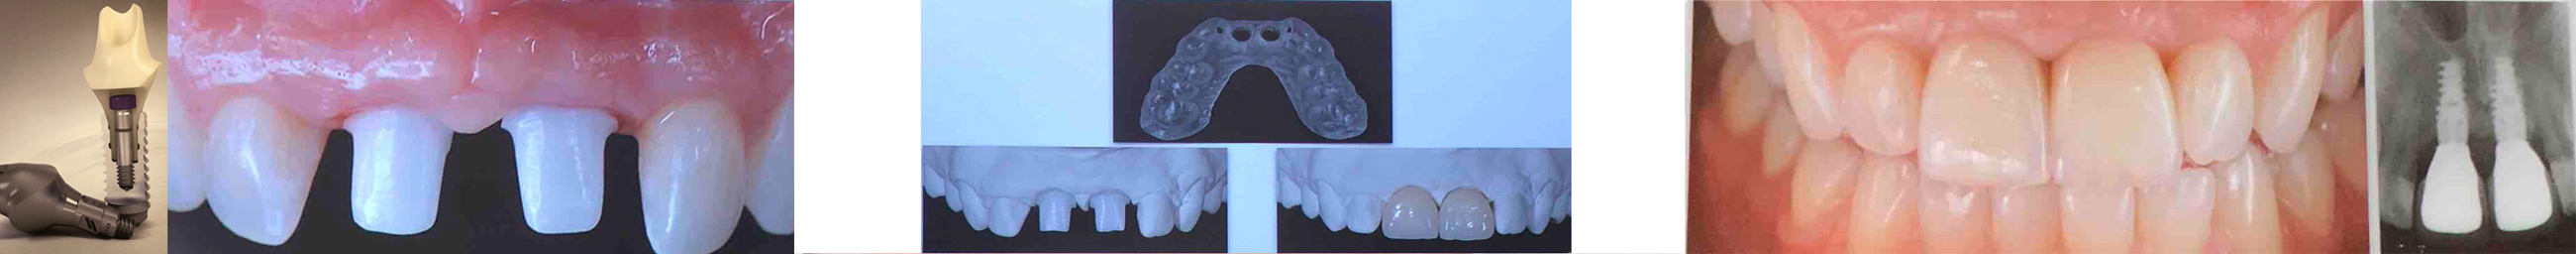

Ψηφιακή αποτύπωση: Λαμβάνονται αρχικά αποτυπώματα για τα οποία μπορεί να χρησιμοποιηθεί ειδικός ψηφιακός ενδοστοματικός σαρωτής (digital intraoral scanner).

Επιπλέον, όταν η αρχική σταθερότητα του εμφυτεύματος επαρκεί, είναι δυνατόν να έχουν προκατασκευαστεί πριν ακόμα τοποθετηθούν τα εμφυτεύματα και οι προσωρινές μεταβατικές αποκαταστάσεις μέσω ειδικού σχεδιαστικού προγράμματος στον υπολογιστή και με ειδικά μηχανήματα κοπής από το εργαστήριο έτσι, ώστε αυτές να προσαρμοστούν στο στόμα αμέσως μετά τη χειρουργική τοποθέτηση των εμφυτευμάτων, να τοποθετηθούν δηλαδή την ίδια μέρα, άμεση φόρτιση (immediate loading).

Σ’ αυτή τη περίπτωση η οριστικοποίηση γίνεται με την κατασκευή της τελικής αποκατάστασης όταν έχει ολοκληρωθεί η επούλωση των ούλων και έχει σταθεροποιηθεί η θέση των περιοδοντικών ιστών.

Μετά την ολοκλήρωση της οστεοενσωμάτωσης (6-12 εβδομάδες, αναλόγως με την περίπτωση) τοποθετείται το στήριγμα (abutment) στο εμφύτευμα, που μπορεί να είναι από τιτάνιο ή υψηλής αντοχής κεραμικό υλικό για περιοχές με υψηλές αισθητικές απαιτήσεις.

Λαμβάνεται το τελικό αποτύπωμα, το οποίο σήμερα μπορεί να γίνει και ψηφιακά, με ενδοστοματική σάρωση(Digital intraoral scanner) και κατασκευάζεται μία μεταβατική αποκατάσταση που κατευθύνει τη σωστή διαμόρφωση των ούλων σε αισθητικές περιοχές και καλύπτει τον ασθενή μέχρι την κατασκευή της οριστικής αποκατάστασης από το εργαστήριο.